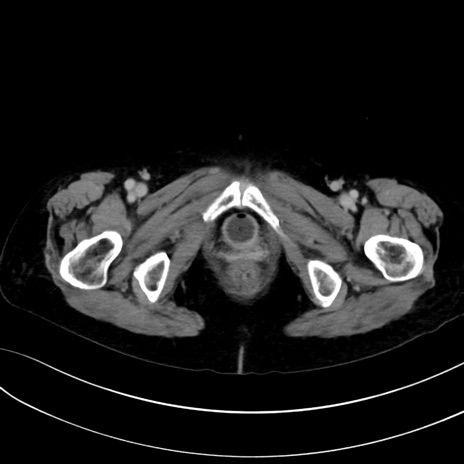

症例13 CT(横断像)1日半後